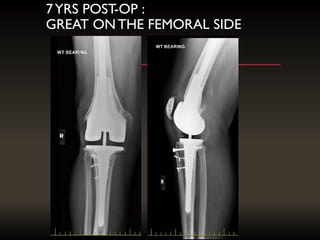

7YRS POST-OP :

GREAT ONTHE FEMORAL SIDE

7YRS POST-OP : GREATONTHE FEMORAL SIDE